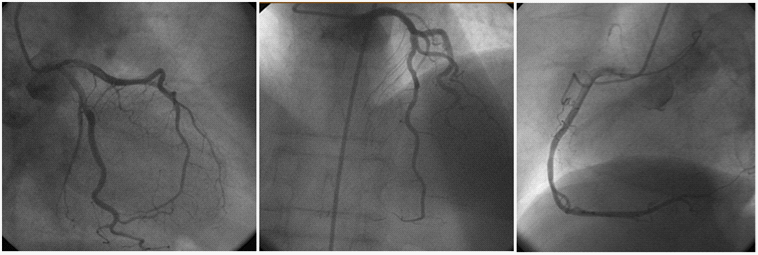

A 77-year-old female patient presenting to the emergency department with chest pain was diagnosed with acute anterior myocardial infarction, but later TTC was discovered. She had squeezing chest pain that started shortly after an emotional stress. The patient had a medical history hypertension. She also noted an argument with her family and neighbor, after which progressed to chest pain associated with mild shortness of breath and sensation of warmth. Ears, nose, and throat exam was negative and there was no jugular venous distension, carotid bruits, or thyromegaly. Breath sounds were clear and equal bilaterally. Cardiovascular exam revealed a regular rate and rhythm without murmurs, rubs, gallops, or clicks. Peripheral pulses were recorded as strong and equal throughout. The abdomen was sensitive, with tenderness diffusely, but no peritoneal signs could be elicited. No femoral, umbilical, or inguinal hernias were palpable. Neurological exam revealed no focal deficit. Extremities were non tender with normal range of motion and no pedal edema. The electrocardiogram revealed a ST-segment elevation in V2 to V4 (Figure 1). Troponin T level was 0.367ng/mL (normal: 0-0.01 ng/mL). After a transthoracic echocardiogram, urgent coronary angiography and ventriculography; coronary angiography was normally, ventriculography had been Aneurysm on anterolateral, anterior and apical valve (Figure 2). TTC was considered and she was started on a β-adrenergic blocking agent and angiotensin converting enzyme inhibitor. Later that day, a repeat ECG revealed resolution of her ST-segment abnormalities. The severe left ventricular systolic dysfunction improved and normalized during the follow-up (6 days). She was discharged without any complications.

Figure 2 Ventriculography demonstrates anteroapical balooning and hyper contractility of basal segments.

Figure 4 Significant coronary artery stenosis is not detected on coronary angiography.